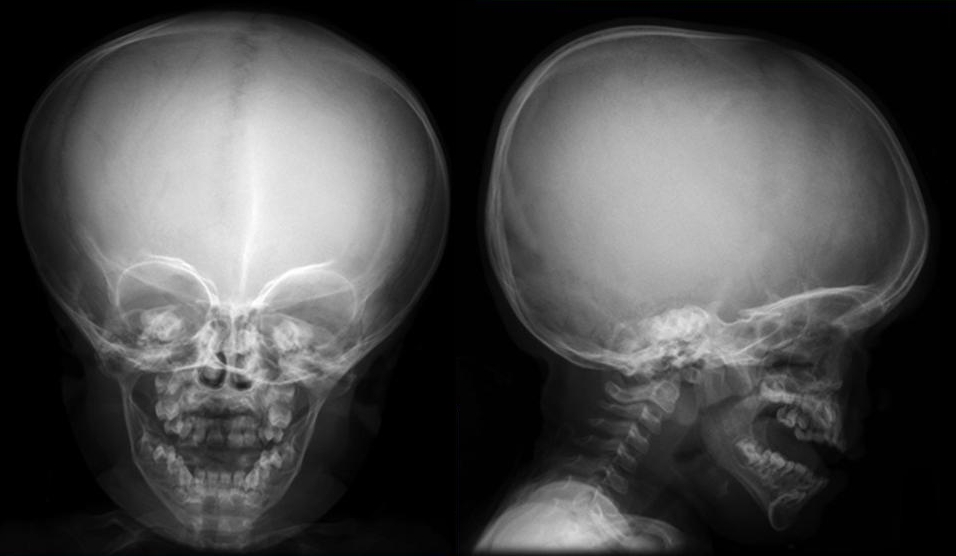

Рентгенография черепа и позвоночника: изображение и диагностика